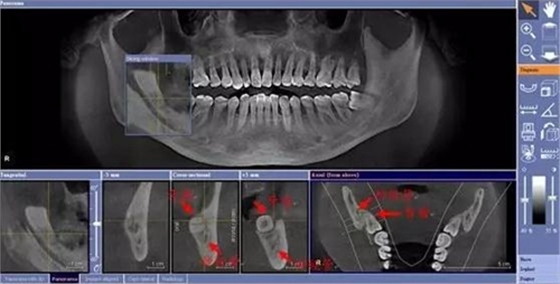

由于智齒的生長位置特殊,導致了拔除難易不同,如智齒出現(xiàn)橫著長或者靠近牙神經(jīng)的話,則難度會較高,一般人只需拍個口腔全景片,但相對于智齒靠近神經(jīng)管的情況,還可能需要拍CT,這都很考驗牙醫(yī)的技術(shù)。

下面這兩張圖,據(jù)說拔牙費時1.5小時,收費14000元。